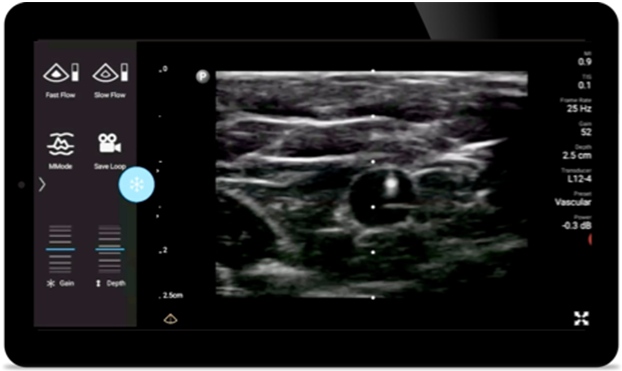

Weniger Komplikationen bei nadelgeführten Verfahren

Lumify Handheld-Ultraschall für die Anästhesiologie unterstützt die klare Konturdarstellung bei der Nadelplatzierung, einschließlich der umgebenden Nerven, Gefäße und Faszienstrukturen.